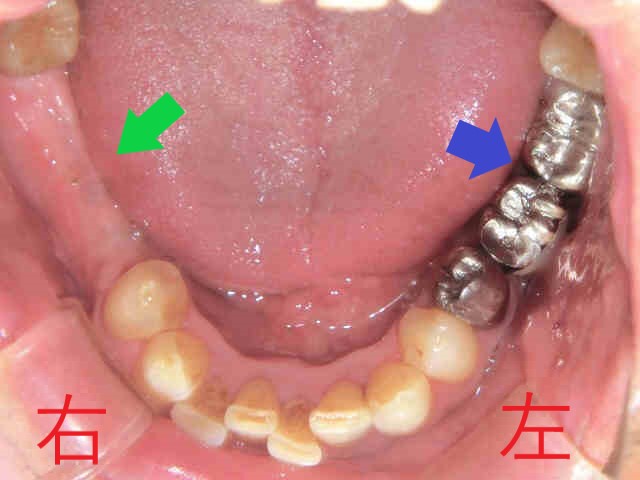

インプラントのご説明の前に、右下の青色矢印にご注目ください。こちらには、2本の歯で3本分の被せ物を支える「ブリッジ」という固定式装置が入っていましたが、後方の歯に大きな虫歯(カリエス)が再発しています(これを「2次カリエス」と呼びます)。

左下のブリッジ(青色矢印)についても、患者様は再度ブリッジによる治療を希望されました。虫歯が大きかったため、神経を除去する処置が必要となり、結果として歯の強度が低下し将来的に歯根破折のリスクが高まる点をご説明のうえ、患者様のご意向を踏まえた治療を行いました。